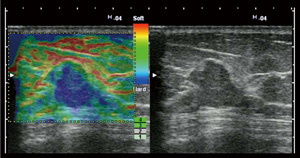

組織の硬さ情報を,画像としてリアルタイムに表示する画期的な技術で,当社が世界に先駆け実用化した技術です。

乳腺の悪性腫瘍の多くは硬いことが知られていますので,超音波検査の際にエラストグラフィを併用することにより,良性悪性の鑑別の一助となるとされています。

エラストグラフィ:粘液癌(乳腺)